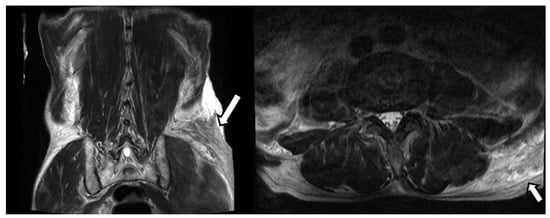

A 77-year-old man visited our hospital’s emergency room with severe low back pain. A few hours ago, while towing a cart, he was in a car accident wherein a vehicle collided behind him. The patient had a history of coronary artery disease for which he was taking an anticoagulant. Several tests were performed, including a CT and MRI of the spine. There were multiple transverse processes, and vertebral body fractures in the examination, so conservative management was performed. Additionally, the MRI image of the lumbar spine showed a curvilinear shape lesion with increased signal intensity in the left buttock region (Figure 1). Similar findings to the above were also seen on abdominal CT (Figure 2). Thus, we considered a subcutaneous edema or hematoma for this finding.

Figure 2. CT scans of the abdomen and pelvis showed an abnormal soft tissue lesion in the left buttock.